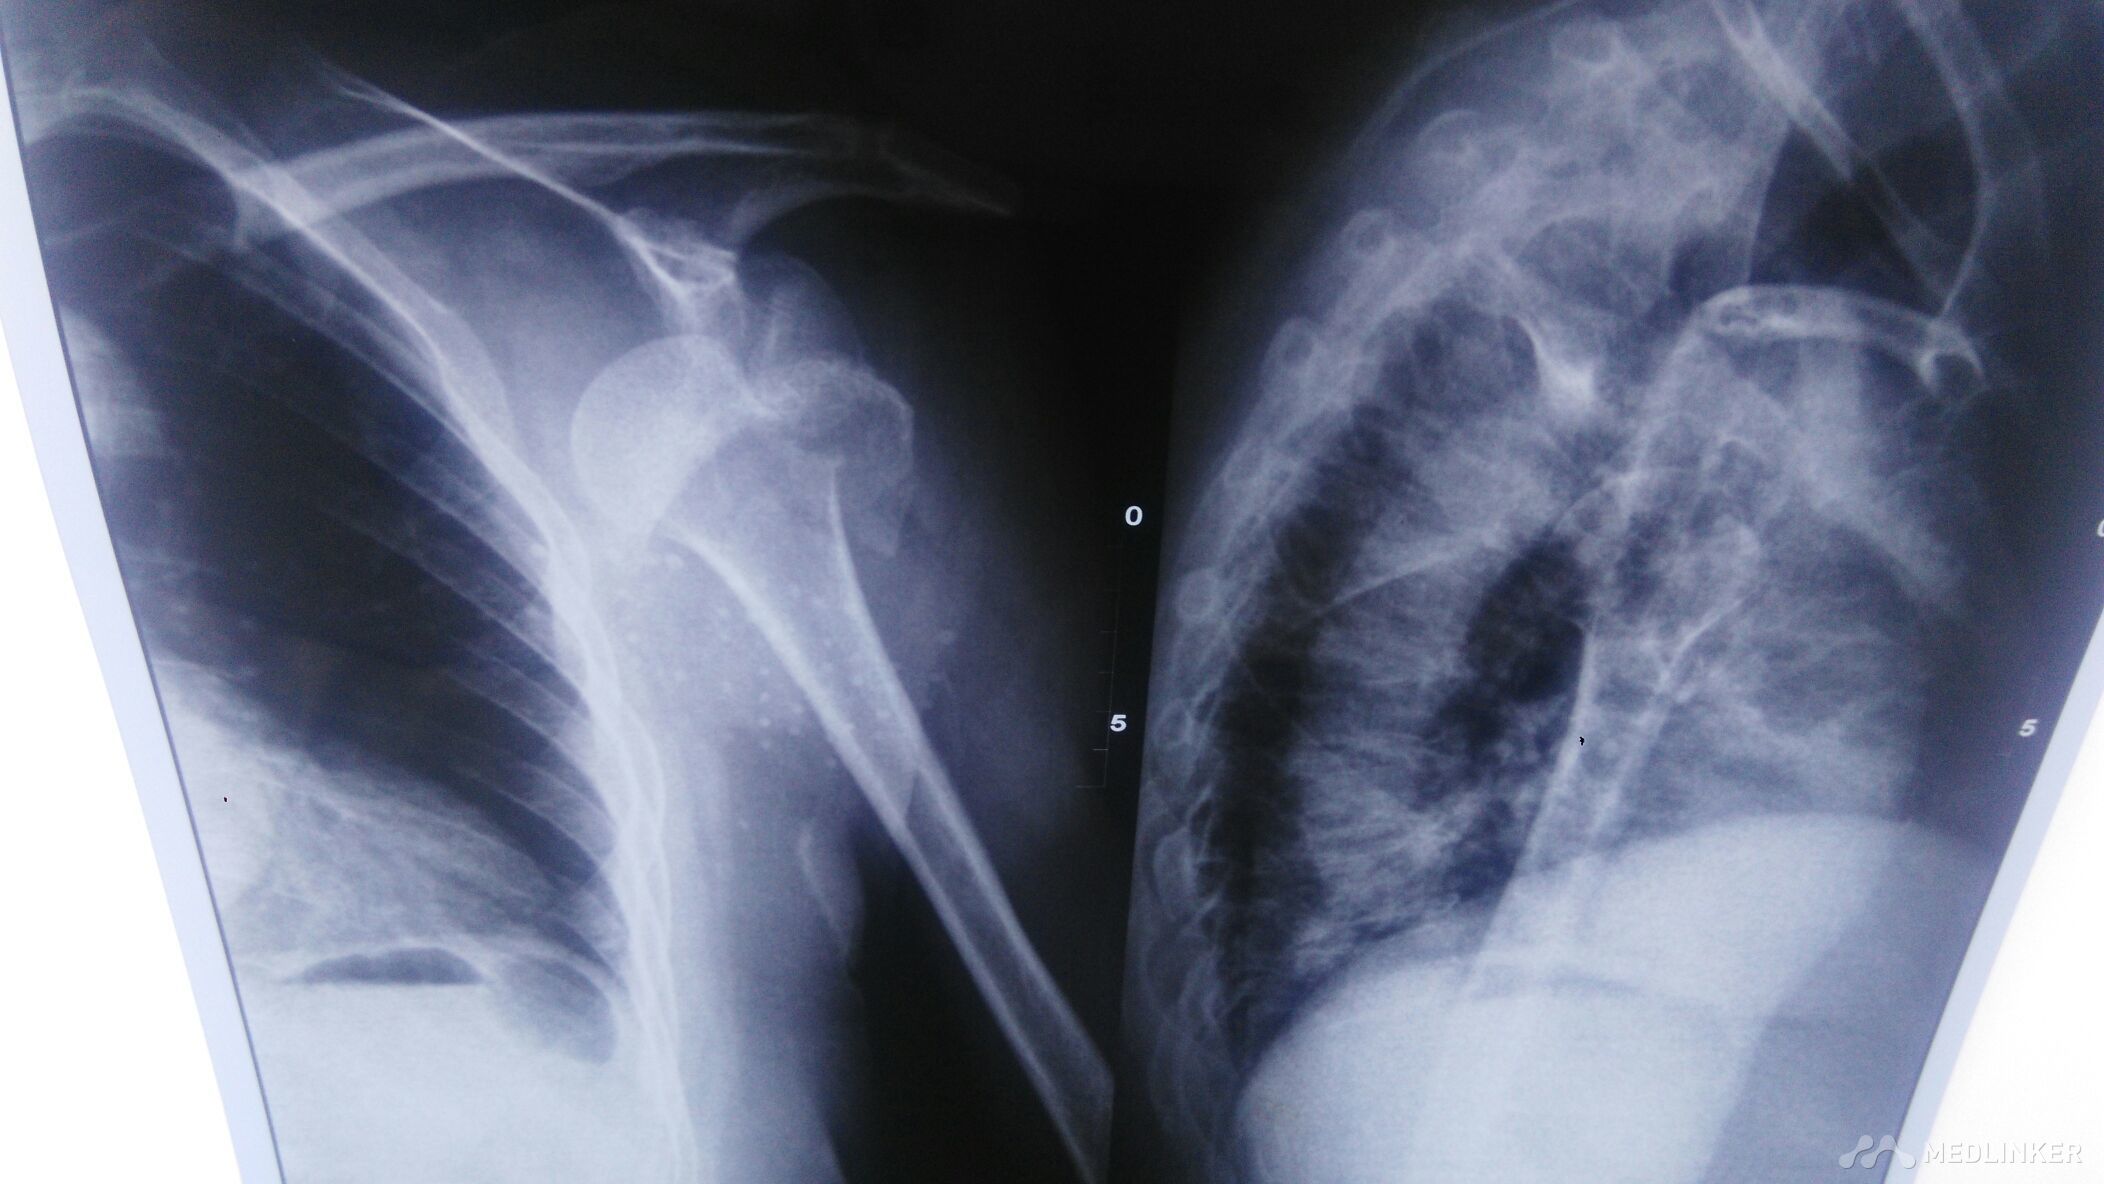

肩部脱位,并大结节骨折。

肩部肿痛畸形,拒按。手部麻木。杜加氏征阳性。肩部叩痛阳性,肩部活动受限。

高龄老人,有高血压病,冠心病史。血压170/110。肩部疼痛难忍。

肩部脱位伴,大结节撕脱骨折。有内科疾病。保守治疗。

只能先降压,适当止痛。犹豫经济条件不好。在局部麻醉下行手法复位治疗。